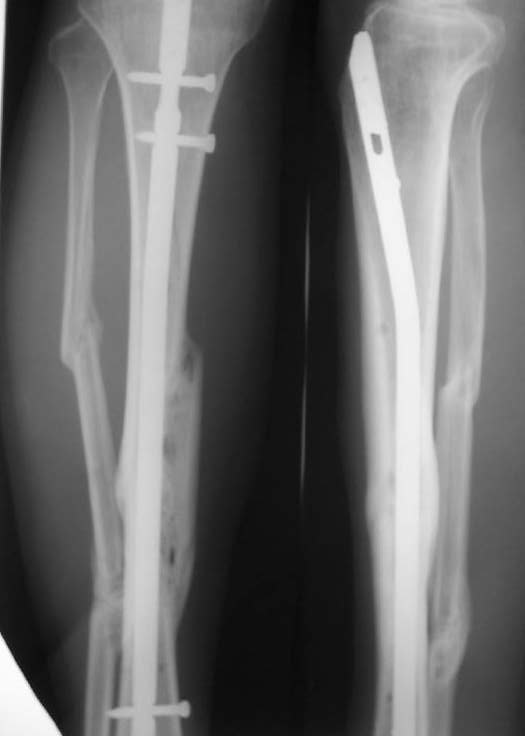

Re: Неправильно сросшийся перелом голени

Александр Николаевич, к сожалению больной не является на контрольные осмотры. Я последний раз видел больного, когда прошло 7 месяцев после операции БОС. У него все хорошо. Каких либо жалоб и ограничений в нагрузке нет. Высылаю снимки до операции и последние снимки.